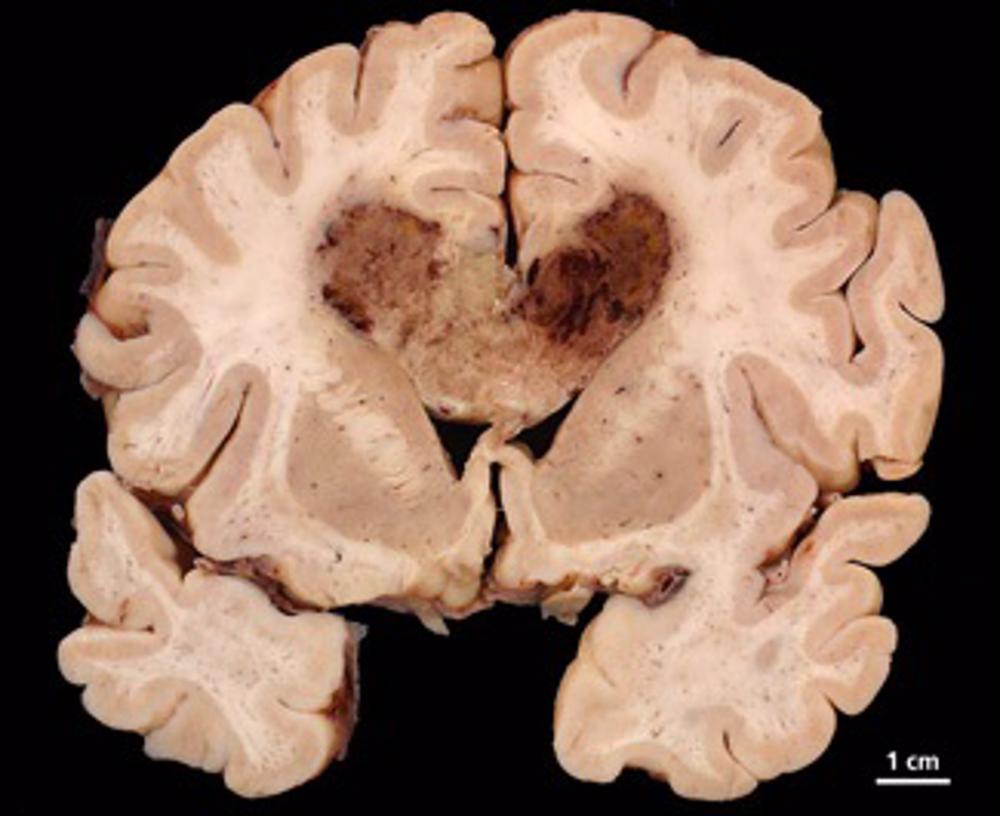

Los tumores cerebrales pueden ser difíciles de tratar, ya sean causados por cánceres cerebrales como el glioblastoma o cuando las células cancerosas se extienden al cerebro desde otras partes del cuerpo. Lamentablemente, son la principal causa de muerte por cáncer en niños y adultos menores de 40 años. La radioterapia es un tratamiento de referencia para los tumores cerebrales, pero en muchos pacientes el tumor se resiste al tratamiento y sigue creciendo.

Este próximo ensayo clínico espera potenciar el efecto de la radioterapia en tumores cerebrales de pacientes que, de otro modo, no responderían al tratamiento.